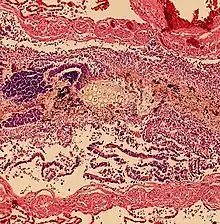

![]() | |

| Upper gastrointestinal series at the level of the esophagus, showing pulmonary aspiration of the radiocontrast agent | |